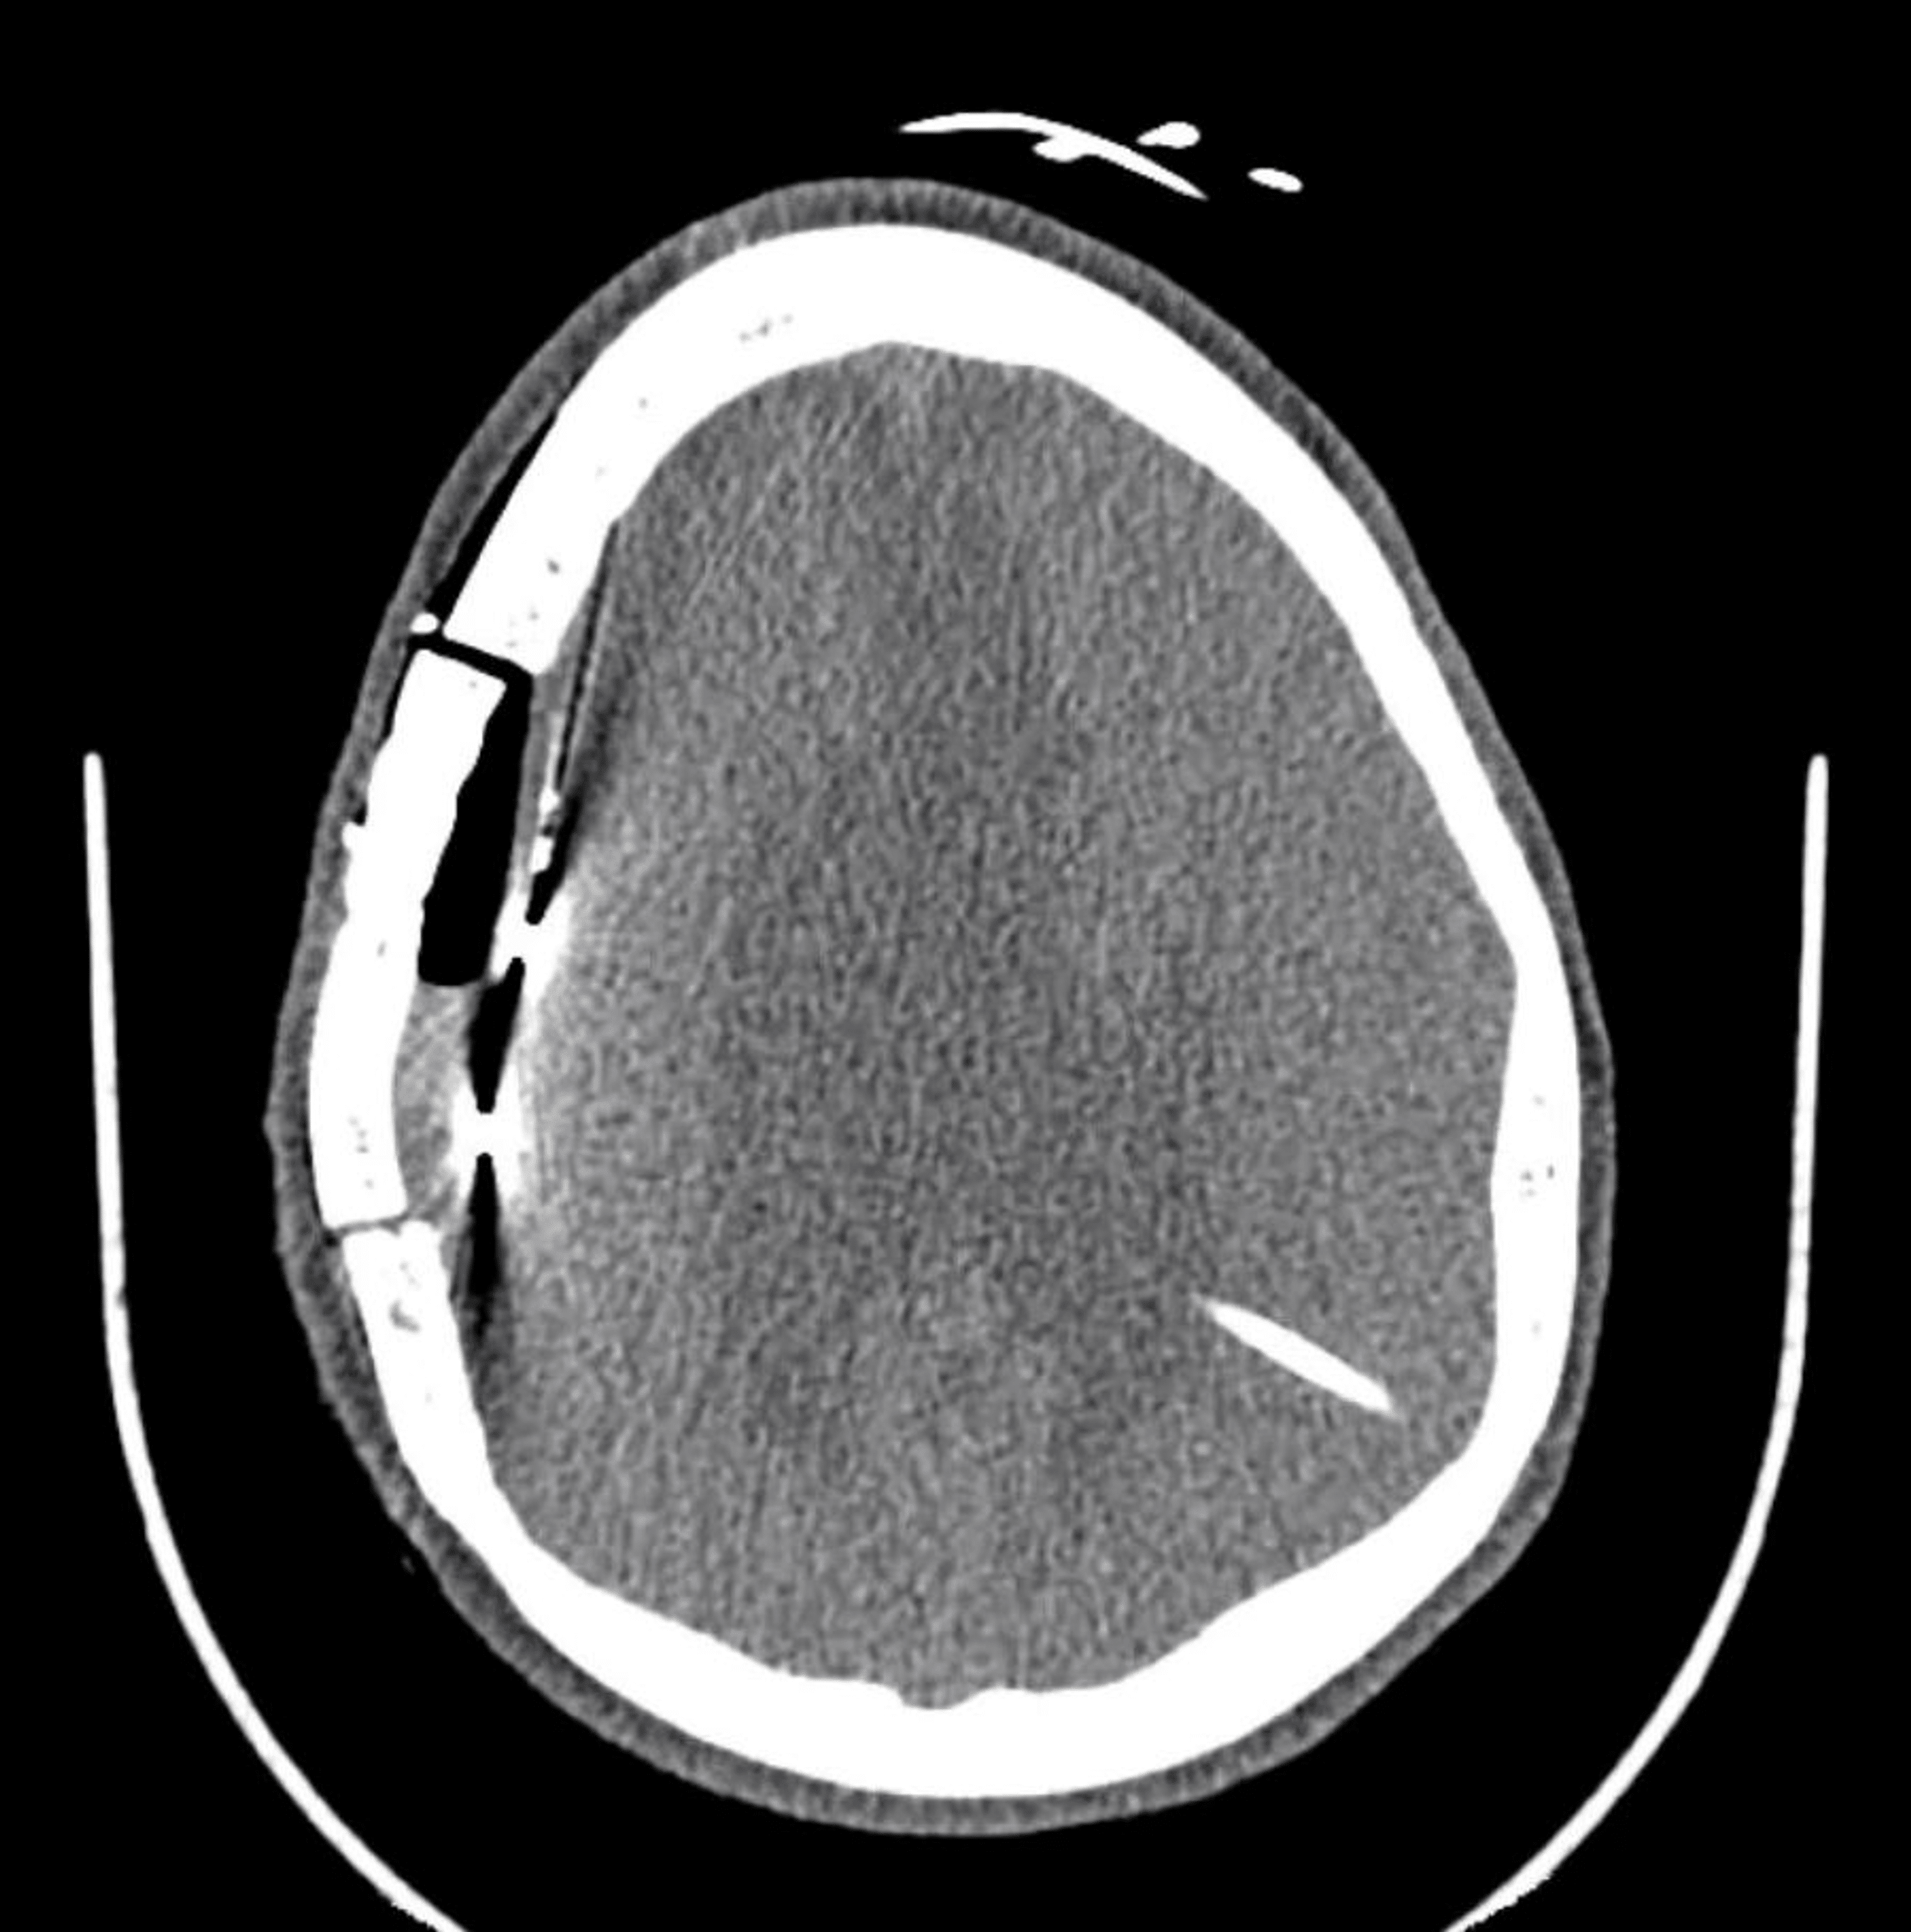

A patient undergoing invasive EEG monitoring with stereotactic depth... Download Scientific Invasive Eeg Monitoring Invasive eeg monitoring involves placing electrodes directly on your child's brain to pinpoint exactly where seizures start. During seeg, doctors place electrodes in targeted brain areas, which are then monitored to precisely locate the source of the seizure. Once your child has surgery to place the electrodes, they will be monitored with a video eeg for three to five. Stephan. Invasive Eeg Monitoring.